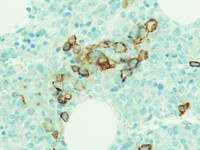

Monoclonal gammopathy of undetermined significance

Haematoxylin-eosin section of bone marrow biopsy showing mild increase in plasma cells

From the collection of Ola Landgren, MD, PhD